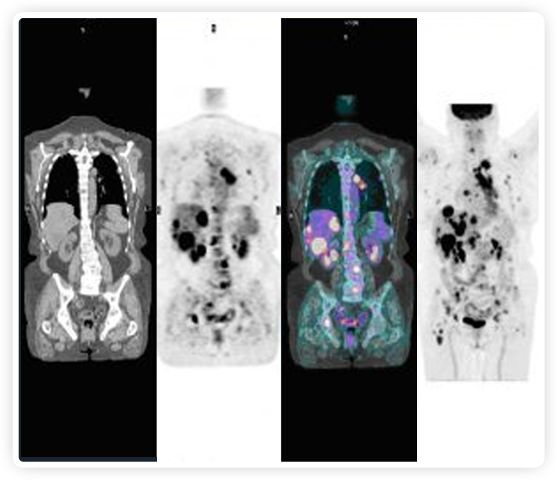

正電子發(fā)射斷層掃描(PET)是癌癥檢測中已建立的成像標準,與其他成像方式相比,PET能提供高靈敏度和特異性的圖像。

到目前為止,放射腫瘤學中(使用的圖像主要是結構性的,而PET圖像可以提供生物學信息。通過使用注射示蹤劑,例如18-FDG,PET可以描繪腫瘤的代謝活性,使其“點亮”。(FDG是用于可視化癌癥代謝的最廣泛使用的示蹤劑。與正常組織相比,腫瘤細胞保留更高水平的FDG。)不同的PET示蹤劑可以識別腫瘤的不同生物學特征,例如特定生物標志物抗原(例如,PSMA)或甚至探測免疫系統本身(例如,PDL1表達或活化的T細胞)。

RefleXion將PET成像與立體定向放射治療相結合。在注射示蹤劑后,RefleXion的技術基于示蹤劑信號實時地在一個或多個目標上引導治療性X射線。使用這種專有方法,RefleXion的平臺有可能比現有系統向癌癥病變提供更高劑量的輻射,并改善周圍健康組織的保護。